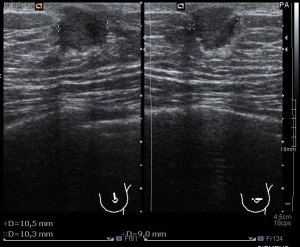

Aquí en la imagen 3 y 4 observas claramente como en el espacio retroareolar observamos una imagen hipoecogénica más larga que alta, heterogénea que está ocupando lo que normalmente debería ser espacio de grasa normal. En la imagen 4 lo que hacemos es realizar las medidas pertinentes, en los planos que consideremos oportunos.